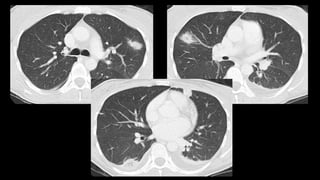

Una mujer de 31 años fue ingresada por faringoamigdalitis pultácea que no mejoró con tratamiento ambulatorio. Presentaba también molestias abdominales, náuseas, vómitos y diarrea. Las pruebas revelaron anemia grave, hipertransaminasemia e infiltrados pulmonares. El diagnóstico final fue bacteriemia por Fusobacterium necrophorum, trombosis de la vena yugular interna izquierda e infiltrados pulmonares, confirmando el síndrome de Lemierre.